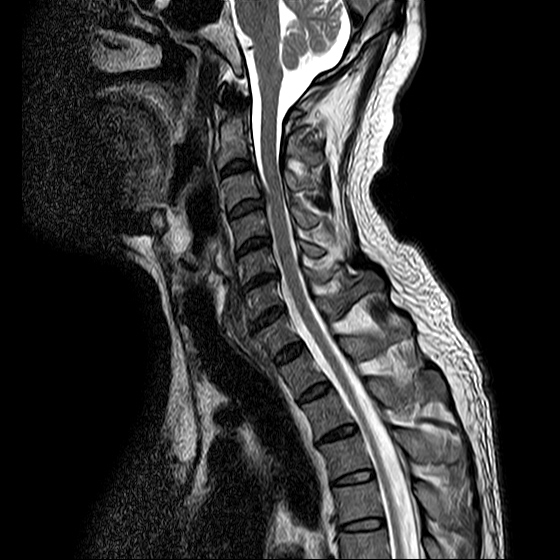

ũ Ͻ е鲲 ǰ ϴ. ڸ 4°Դϴ. ũ ϴ. (ڸǥغ ǥغ ) @ : 2014. 2.15 ĺ Ȳġ Ͽ. -> κ ǿ ġϿ պ ϱ. @ 2014. 3. 27 к mri, ct ũ ϰ ؾ Ѵٰ. @ ũ ġ ͳ Ͽ ڸǥغ Ͽ. ϱ : .(ó ) 2014. 4. 12() --- <1°> : Ͽ ȸ . 㳻 : (ڱ , Ӹ е ħ ˷. ¿ . ų ɰų Ҷ ̰ų ڼ . 201.4. 4. 13() ---<2°> 1. ħ Ͼ ¿ ȭ . 2. ħ е ħ . 3. ü ƮĪ ˷. ڼ ˷ֽŴ ϸ ڼ ùٸ ϸ Ÿ ˷ֽ Ư ƮĪ ϸ Ѱ پ 2014. 4. 14() ---<3°> : : پ(ó ߴ.) 㳻 : 1. ħ Ͼ ¿ ȭ . 2. ũ ˷ . 2014. 4. 14() ---<4°> : پ(ó .) 㳻 : 1. 繫ǿ ũ ٽ 2. ũ ˷ ϸ ڼ ϸ ȸ ̷ ɴ 2~3 ϸ ȸȴٰ Ͻô ū 븦 Ͽ ȸϵ ϰڽϴ. ȸ Ź帳ϴ. ũ mri Ȳ Դϴ. Ű 179 86 51 ()ijħ ڸǥغ ǥغ ˰Ե ͳ ˻ڷ õ ()ijħ ڸǥغ ǥغ ϱ ȣϽ 6C.ڸ 6C.ھ Ḳ 7C.Ȳġ 1T.Ȳġ 1T. κ ()ũ( ߰Ż) ڸ(߹) ũ(߰) Ը ũ(߰Ż)ġ, ()ijħ ڸǥغ ǥغ ϰ ߴ ġ 1. : 2014. 2.15 2. ġ : Ʒ(ô߿ ) , ȱ 3. **뺴 : ˾. Ƽ (ũ ) 4. ó : ڰ, 3 Ⱓ mypol()ó. ȭ. 3 5. ü ġ . |